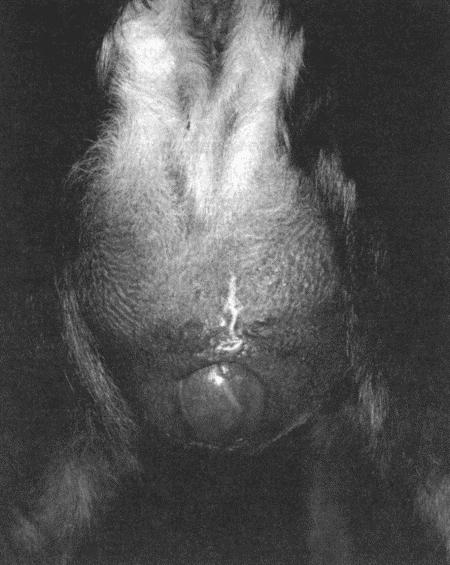

Вагинальная эндоскопия

Прекращение секреции эстрадиола фолликулами и переход их к секреции прогестерона приводят к снижению как отечности, так и васкуляризации слизистых оболочек, что сопровождается выраженным изменением характера вагинальных выделений, выявляемым с помощью вагинальной эндоскопии. На стадии проэструса слизистая оболочка становится более выпуклой и отечной, затем наблюдается ее уменьшение; по мере приближения овуляторного пика слизистая сжимается и бледнеет, в некоторых случаях становясь практически белой (фиг. 1.1). Перечисленные изменения свидетельствуют о приближении стадии, характеризующейся постепенным повышением концентрации прогестерона перед овуляцией и последующим наступлением фертильного периода. Эти изменения легко узнать, имея даже небольшую практику (фиг. 1.3), кроме того, они настолько воспроизводимы, что по набору признаков их можно оценивать полуколичественно. Вагинальная эндоскопия весьма полезна в определении оптимальных сроков вязки. По окончании фертильного периода, т. е. в начале метэструса — слизистая оболочка влагалища бледнеет и истончается, складки становятся закругленными — и что, вероятно, является наиболее характерным признаком, — слизистая в переднем отделе влагалища выглядит раздраженной и при прикосновении быстро сжимается, образуя розетку.

Фиг. 1.3.

Эндоскопическое исследование слизистой влагалища. Динамика изменений на протяжении цикла: (а) проэтрус — розовая окраска и отечность; (b) начало эструса — слизистая бледнеет, отек начинает уменьшаться (обычно перед пиком ЛГ); (c) середина эструса — слизистая бледная, уменьшение отека (сморщивание) явно выражено, что соответствует середине фертильного периода; (d) начало метэструса — видны закругленные складки, при прикосновении слизистая смыкается, образуя розетку (е) (см. Приложение)